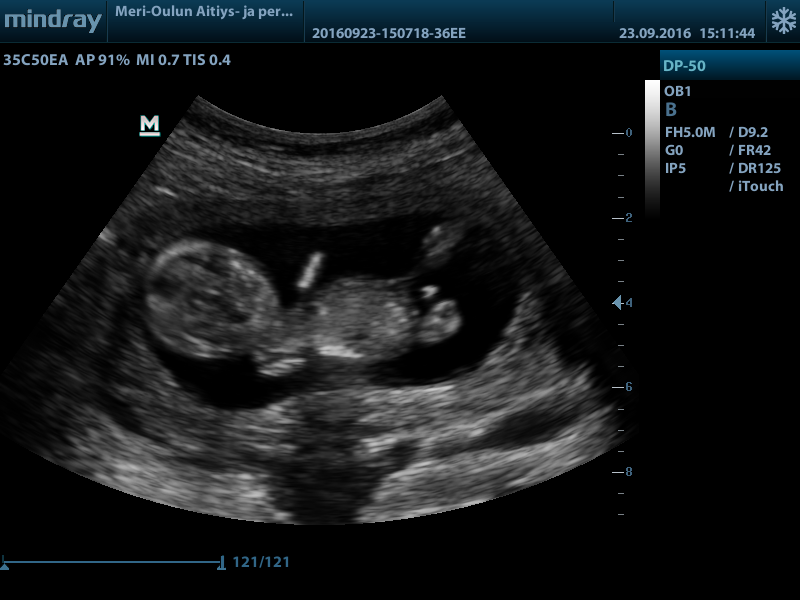

Hi! Would love your thoughts regarding the gender. Boy or girl? (And maybe why, I'm really new at this.. )

Top of the baby isn't the best for nub guessing but at 13 weeks girl parts wouldn't be so...large... At that gestation. I'm a few of the pictures I am almost positive I see testicles too so my guess is boy :) will actually be a little shocked if you hear girl please update when you know!